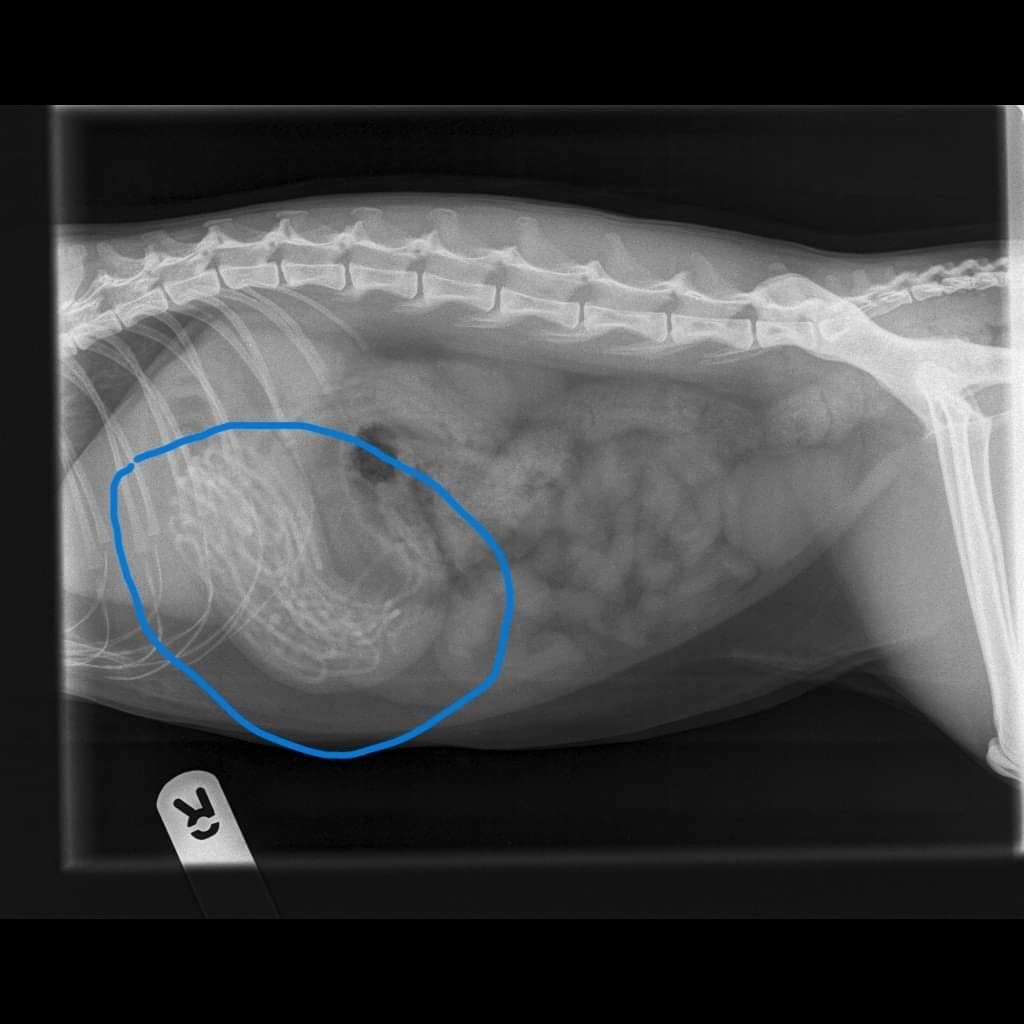

Marley's owners hadn't even noticed he'd been eating the bands until he fell ill but X-rays revealed the three-year-old feline had a huge mass, over 30, in his stomach.

But they were shocked to find a mound of hair ties taking up "around 80%" of Marley's stomach, which were thought to have built up over “quite some time.”

"X-rays were carried out and that's when they noticed there was a big mass in his stomach.

"But it wasn't until they opened him up that they realised it was a clump of hair bobbles along with elastic bands and string - things we didn't know he was eating."

Vet Nick Whieldon carried out the surgery on Marley, and said: "We could feel that Marley's stomach was almost entirely full of material and when we opened it up we found he'd eaten a lot of hair bobbles.